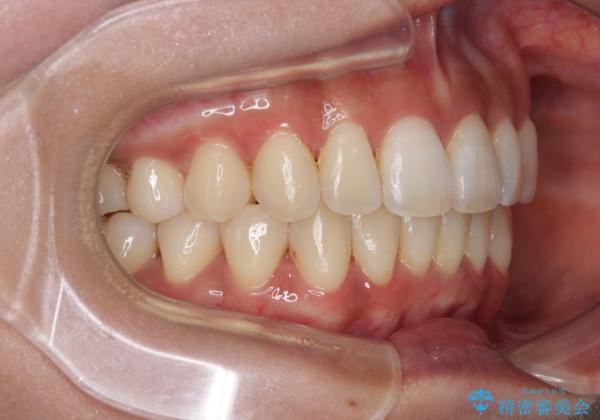

【モニター】上顎前突と奥歯の鋏状咬合 補助装置を用いたインビザライン矯正治療

- 前歯の歯列不正と奥歯の咬みにくさを気にして来院された患者様です。

インビザラインでの矯正治療を希望されていましたが、奥歯の咬み合わせがインビザライン単独では改善困難と判断されたので、補助装置を併用することとしました。

上顎最後臼歯は極端に外側を向いており、下顎骨に対して上顎骨が前方に位置していたため、補助装置により最後臼歯を一気に内側に引き込むとともに、上顎臼歯を後方移動させ、奥歯の咬み合わせが改善した後に、上下インビザラインにより歯列全体を整えていくこととしました。

奥歯の咬み合わせを事前に望ましい位置に改善したことで、インビザライン単独では改善が最も困難な状況を排除することができ、非常に理想的な仕上がりとなりました。